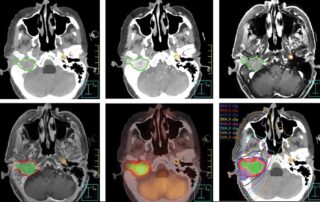

Nº1: Cáncer de cara recurrente relacionado con exposición laboral a campos electromagnéticos en el interior de una vivienda.